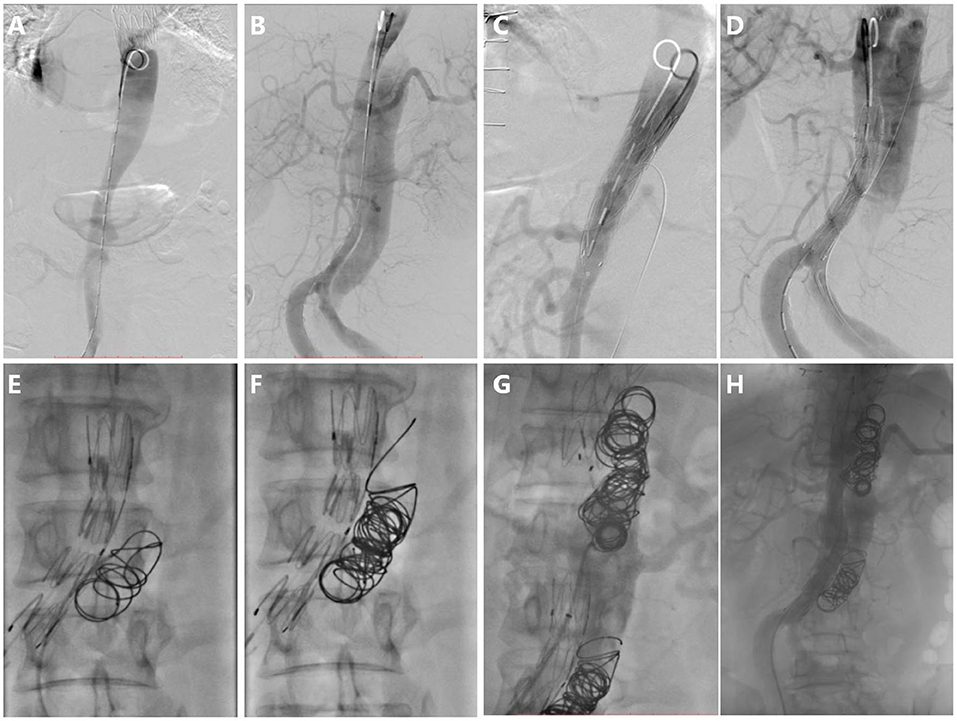

For the second step of RBS, 7.7 ± 4.1 (range 2–18) coils were used in each patient. Coils were placed in the true lumen in 5 patients (38%) and the visceral artery in 3 patients (23%) during embolization, and successfully repositioning was observed in all cases. The coils were extended to the rest of the FL; care was taken to avoid excluding visceral arteries. A total of 4 patients (30%) underwent Onyx glue injection (mean volume of glue injected was 0.9 ± 1.7 ml), and 3 patients (23%) underwent occluder placement due to a large FL (minimum FL diameter > 20 mm) (Figure 4). Intraoperative angiography can be seen as Figure 4.

Figure 4. Intraoperative angiography. (A) Digital subtraction angiography in the true lumen, (B) Aortography in the FL, (C) Stent deploying at tears distal to visceral artery, (D) Preserving tear which is proximal and supplies blood to the visceral artery, (E) The first coil was released and drifted to the initial point in the FL, (F) More coils were released from the initial point, (G) Repeating procedure F and forming segmental thrombosis, and (H) Aortography after RBS, showing blood flow decrease in the FL apart from the necessary blood flow track.